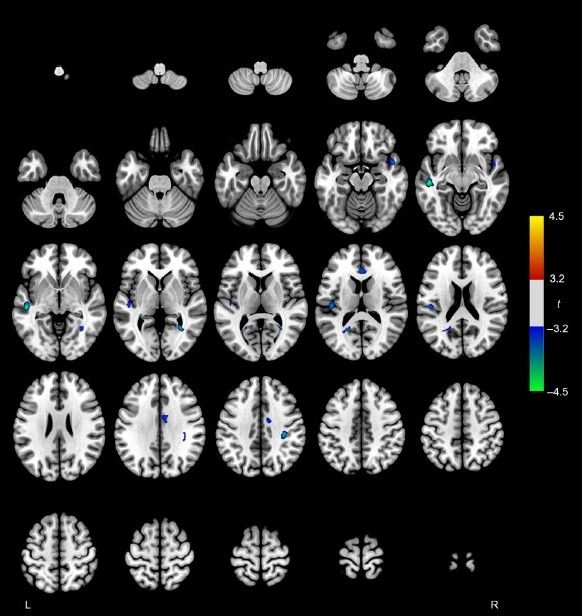

onlinelibrary.wiley.com/doi/full/10....

#neuroimaging #neurology #neuroskyence #radiology #glioma #restingstate #fMRI

onlinelibrary.wiley.com/doi/full/10....

#neuroimaging #neurology #neuroskyence #radiology #glioma #restingstate #fMRI